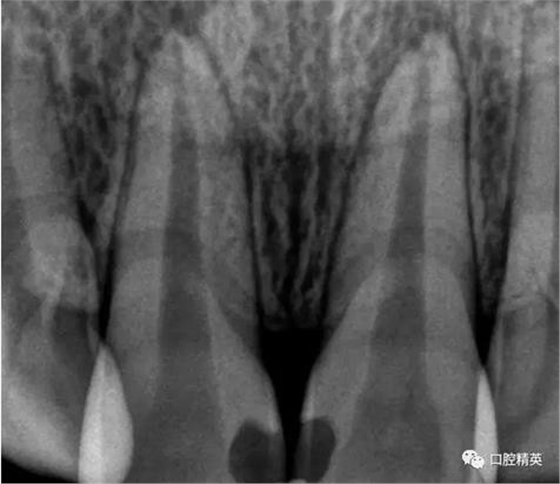

檢查:11,21近中鄰面可見(jiàn)樹(shù)脂類充填體,兩牙唇側(cè)根尖部有膿包狀突起,觸診疼痛,11,21無(wú)松動(dòng),叩診稍有不適,冷熱診檢查無(wú)反應(yīng),X-ray示11,21充填體底部近髓,根尖區(qū)無(wú)明顯異常影像。

診斷:11,21牙髓壞死,根尖炎

術(shù)前檢查

齲洞低已近髓